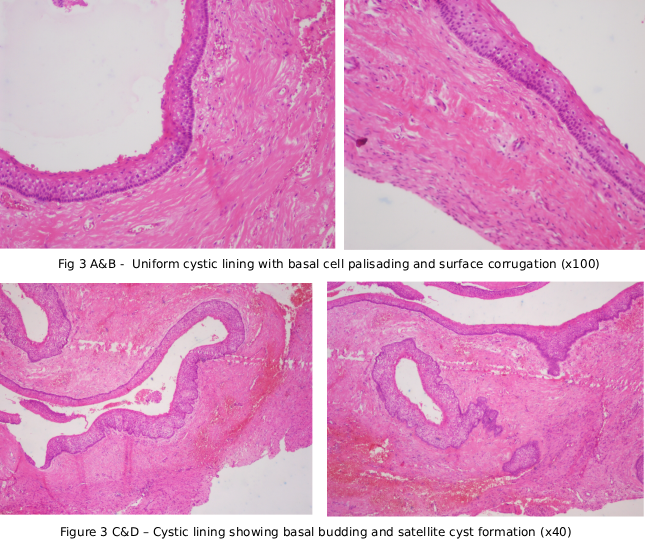

Case Study 3

Final Diagnosis: CONVENTIONAL AMELOBLASTOMA (Solid Multicystic Ameloblastoma)